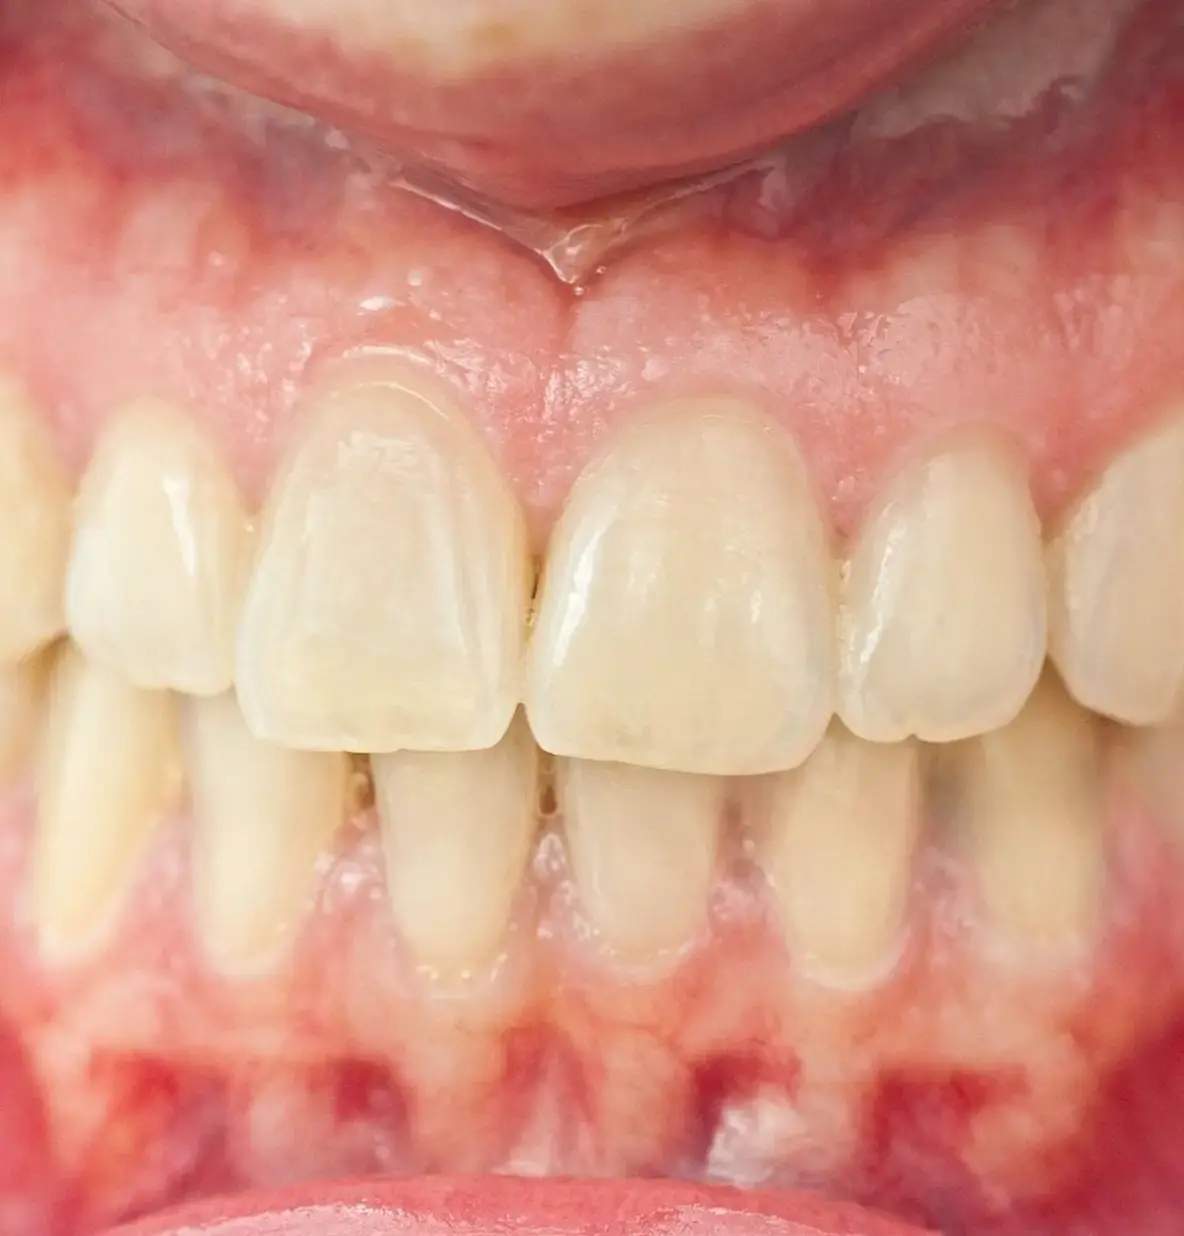

Симптомы мезиальной окклюзии: Вид сбоку: массивный, выступающий вперед подбородок. Нижние зубы перекрывают верхние, формируя так называемое обратное смыкание. Вид спереди: «вогнутый» профиль лица, западение верхней губы. Происходит нарушение контакта между передними зубами и появляются проблемы с откусыванием пищи.

Неправильное распределение жевательной нагрузки вызывает преждевременное стирание и повреждение зубов.

Повышенная нагрузка на зубы и трудности с поддержанием гигиены приводят к развитию заболеваний пародонта и десен. Регулярная чистка, профессиональная гигиена и устранение факторов риска помогают предотвратить воспалительные процессы.